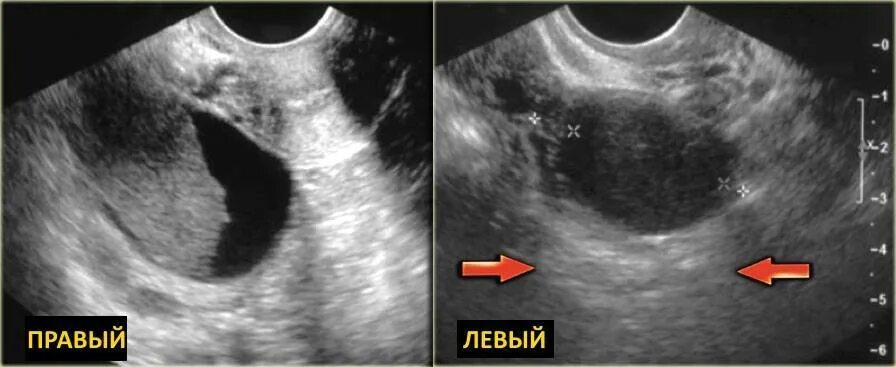

Эхо признаки кисты